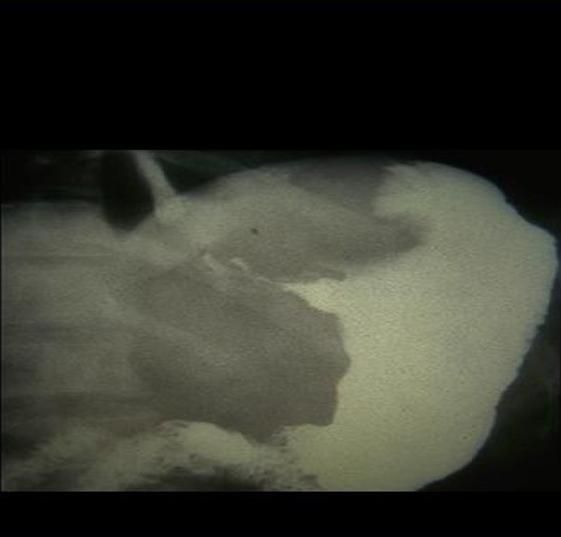

Petit ulcere a petit

courbure infiltration cancereuse a grande courbure . |

Grande ulcere antral et

bourerelet oedemateux . Lesion ulceriforme de type 3

|